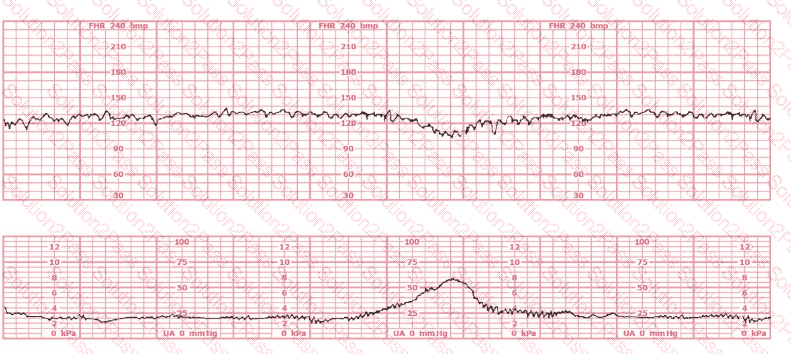

The pattern on the fetal heart rate tracing shown is likely due to

The tracing shown is from a woman at 28-weeks gestation in the post-anesthesia care unit (PACU) after an appendectomy. She is alert and awake. Based on this fetal heart rate pattern, the most appropriate intervention is:

The fetal heart rate tracing shown demonstrates:

The tracing shown is a: